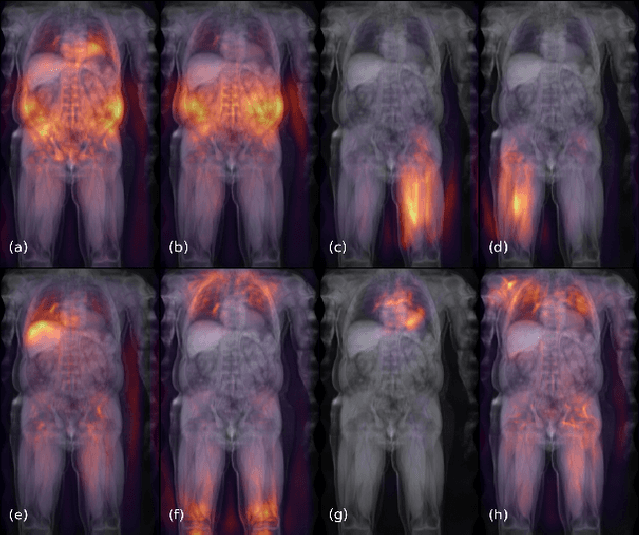

Abstract:Objective: Automated analysis of MRI with deep regression has the potential to provide medical research with a wide range of biological metrics, inferred at high speed and accuracy. Methods: The UK Biobank study has successfully imaged more than 32,000 volunteer participants with neck-to-knee body MRI. Each scan is linked to extensive metadata, providing a comprehensive survey of imaged anatomy and related health states. Despite its potential for research, this vast amount of data presents a challenge to established methods of evaluation, which often rely on manual input. In this work, neural networks were trained for regression to infer various biological metrics from the neck-to-knee body MRI automatically, with a ResNet50 in 7-fold cross-validation. No manual intervention or ground truth segmentations are required for training. The examined fields span 64 variables derived from anthropometric measurements, dual-energy X-ray absorptiometry (DXA), atlas-based segmentations, and dedicated liver scans. Results: The standardized framework achieved a close fit to the target values (median R^2 > 0.97). Interpretation of aggregated saliency maps indicates that the network correctly targets specific body regions and limbs, and learned to emulate different modalities. On several body composition metrics, the quality of the predictions is within the range of variability observed between established gold standard techniques. Conclusion and Significance: The deep regression framework robustly inferred a wide range of medically relevant metrics from the image data. In practice, this technique could provide accurate, image-based measurements for medical research months or years before the more established reference methods have been fully applied.